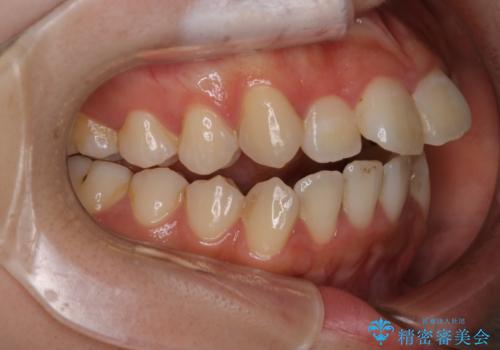

【インビザライン】マウスピースで開咬改善

- 開咬を主訴に来院されました。

IPR(歯と歯の間を削る処置)と顎間ゴムを行いながら、インビザラインで開咬を治療する計画を立てました。

治療をしながら、MFT(口腔筋機能療法)も行っていくことにしました。

歯の移動量が多いケースでしたが、患者様にマウスピースの使用とゴム掛けを頑張っていただいたので

リファイメント1回のみで治療を終わることができました。